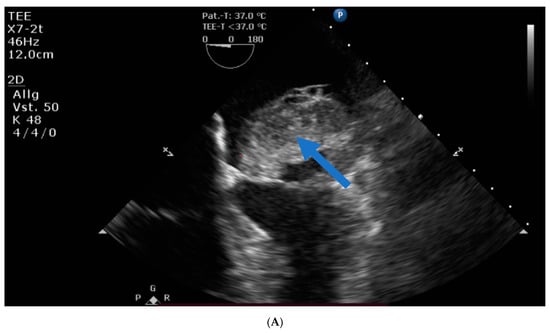

Transthoracic and transesophageal echocardiography revealed a large mass (40 × 60 × 24 mm) in the left atrial lateral wall, extending to the mitral valve (Figure 1A,B). Both atria were severely dilatated. The left ventricle was normal in size with an ejection fraction of 55%, an apicolateral/midlateral hypokinesia and a mild diastolic dysfunction. The normal-sized right ventricle had impaired systolic function. A hemodynamically irrelevant pericardial effusion was present.

Figure 1.

(A) Huge left atrial mass (arrow indicates cardiac mass). (B) Huge left atrial mass prolapsing into the mitral valve in diastole and thus obstructing the inflow of the left ventricle (arrow indicates cardiac mass).